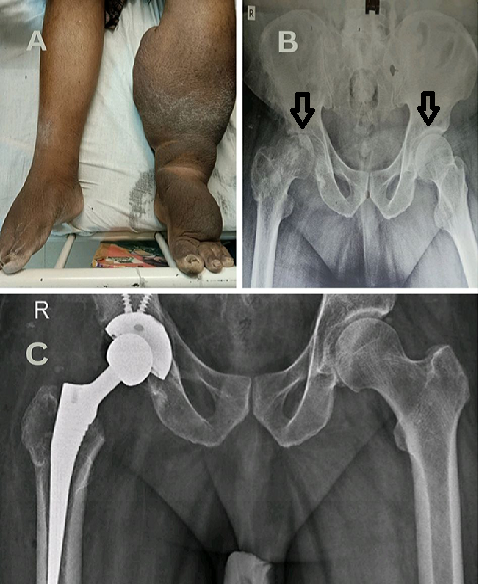

Rare clinical image of chronic bilateral lymphatic filariasis with secondary bilateral hip osteonecrosis

Osteonecrosis of the femoral head (ONFH) is a progressive disorder caused by vascular compromise to subchondral bone, leading to joint collapse and disability. It is associated with multiple risk factors, but its coexistence with chronic lymphatic filariasis is rarely reported. Early diagnosis and management are crucial to prevent irreversible hip destruction. This case highlights the rare association of chronic lymphatic filariasis with bilateral femoral head osteonecrosis, the limited benefit of core decompression in advanced disease. A 52-year-old male, known case of bilateral lymphatic filariasis for forty years, presented with progressive dull aching pain in the right hip and difficulty in ambulation for one year. The pain was progressive, aggravated by weight-bearing and relieved by rest. Six months earlier, he had undergone core decompression with bone grafting, without symptomatic relief. Subsequently, symptoms worsened with functional limitation. Radiographs revealed bilateral avascular necrosis of femoral heads (R>L), and the patient underwent right total hip arthroplasty with physiotherapy rehabilitation.